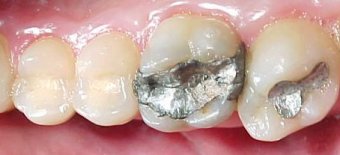

ANTES DEPOIS

Substituição de restaurações em amálgama de prata por resina composta no segundo pré-molar e por ONLAY ARTGLASS no primeiro molar.